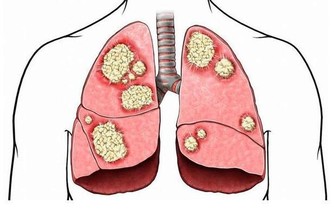

血脂異常患者的四週健走計畫血脂異常是指血液中膽固醇和中性脂肪過多的狀態,為了預防或改善血脂異常,必須減少壞膽固醇和中性脂肪,同時增加好膽固醇。血脂異常的患者應該以全力之50%的強度,在呼吸不會感覺吃力的狀態下,快步健走15分鐘以上。

除了運動之外,也要注意飲食不要過量,增加膳食纖維,剋製甜食、

高膽固醇食品(雞蛋、鱈魚卵、魩仔魚、鮭魚卵、海膽等)的攝取等,也有助於改善及預防血脂異常症。